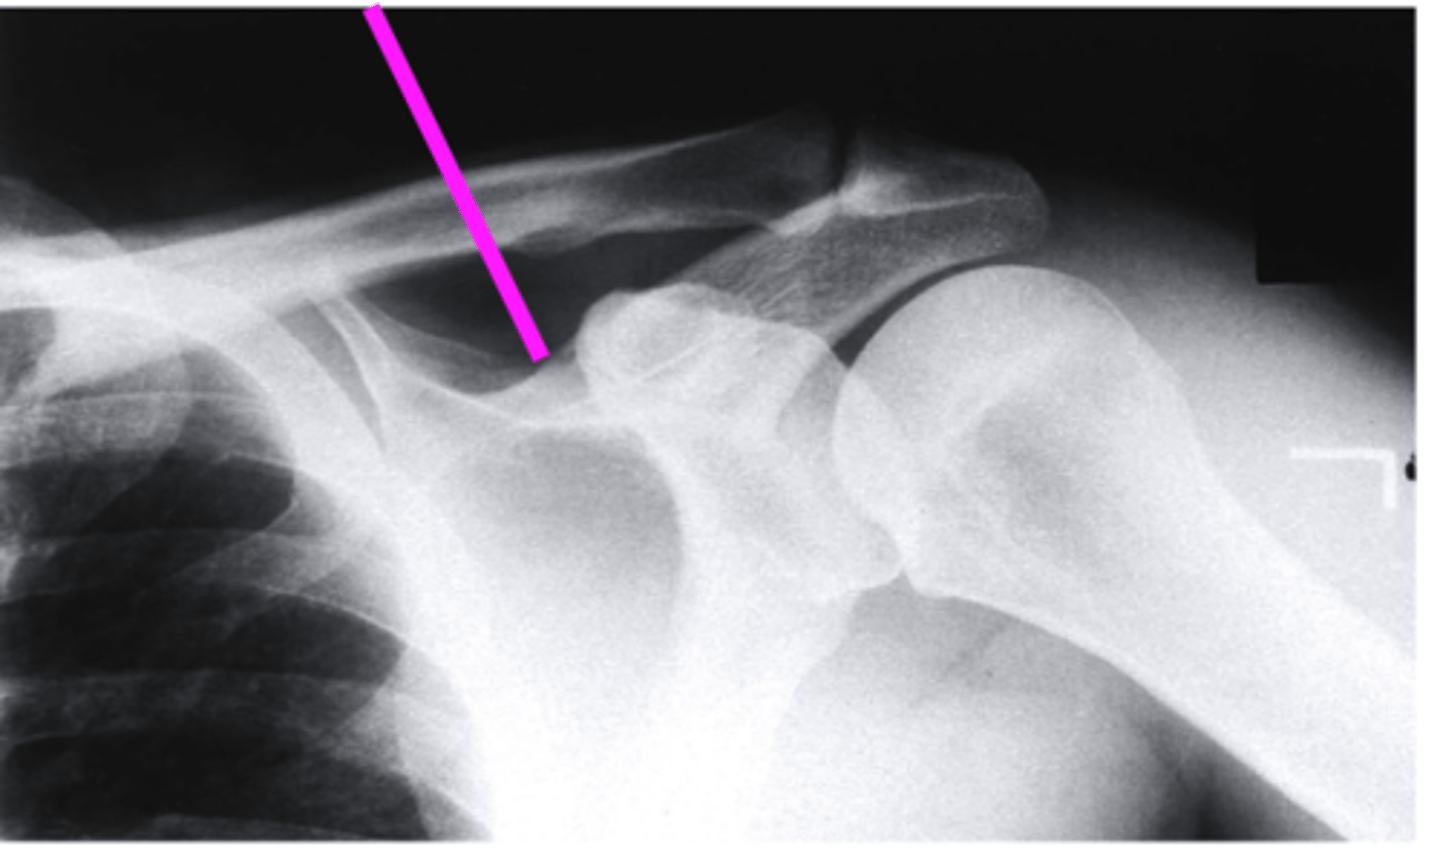

AP + IR

what view is this?

clavicle

what does the pink line point to?

spine of scapula

coracoid process

glenoid fossa of scapula

AC joint

acromion

Humeral Head

lesser tubercle